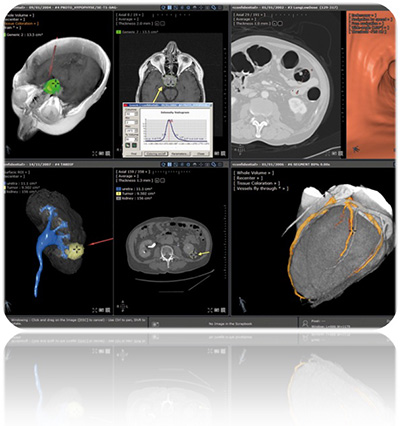

・アドバンストマルチモダリティビューア/カスタムビューアツールキット“Myrian”